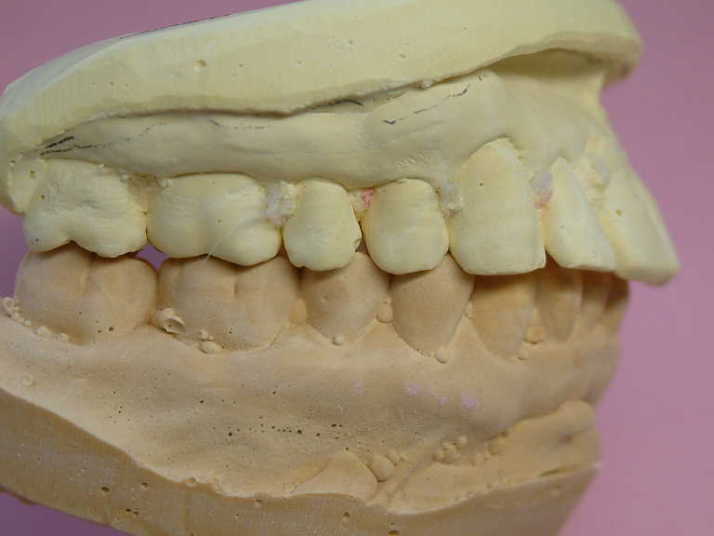

先生方よりテックより少し短くとか、内側に入れて

等のアドバイスを頂いてからMBの製作に

取りかかります。

テックをもとにした打ち合わせを行っているので

ワックス試適、ビスケットベイク試適など

は行っていません |

初診と最終補綴物

患者さんにも満足して頂けた最終補綴物 |